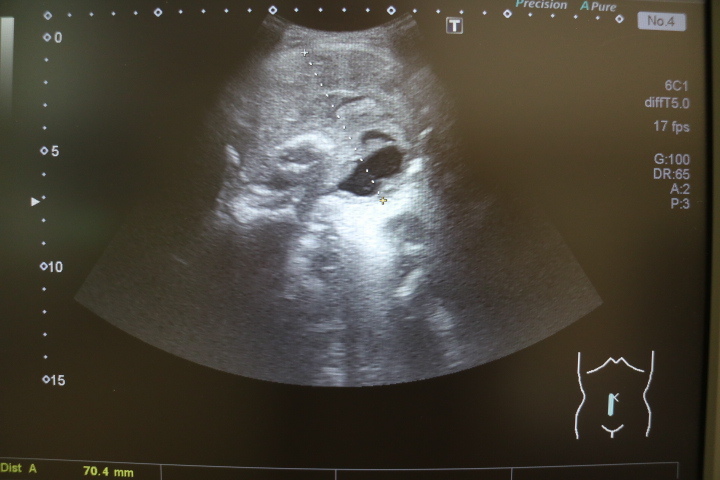

超音波検査(腹部・頸部・四肢など)

・腹部超音波検査(肝臓・胆嚢・膵臓・腎臓・前立腺など)